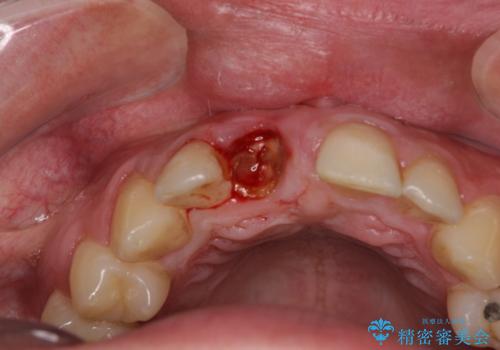

磨き残しなどによるプラークの付着が多いため、仮歯の用意と手術アポイントの調整を行っている間に口腔内のクリーニングなどを施し、環境がある程度改善されたのちに、抜歯即時インプラント埋入、即時荷重(インプラント埋入時に仮歯の装着)の予定で治療を行うこととしました。

度重なる脱離により、表側の炎症が非常に強くなっており、歯を支える骨が失われている状態でした。

そのため、現在の位置よりも歯と歯肉の位置が退縮する方向に移動する可能性があり、前歯2本の歯肉位置が大きくずれることとなるため、本人との相談のうえ、天然歯が萌えているような歯肉状態とはならないものの、2本の段差が少ない状態にて治療を終えることとなりました。